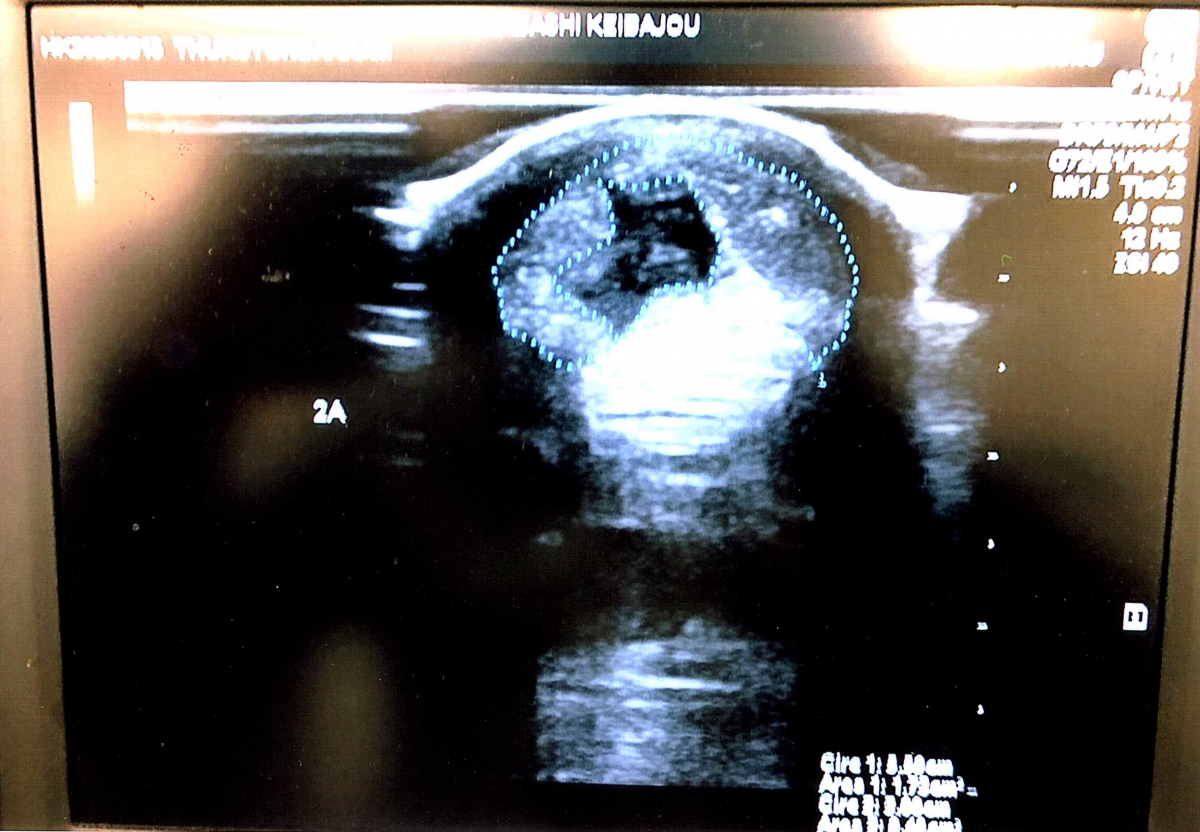

※2023年3月13日の競走にて左前屈腱炎(損傷部位1B~3B 最大損傷部位2A 損傷率27%程度 コア型)を発症。事故見舞金を受給しています(添付の画像をご確認ください)。